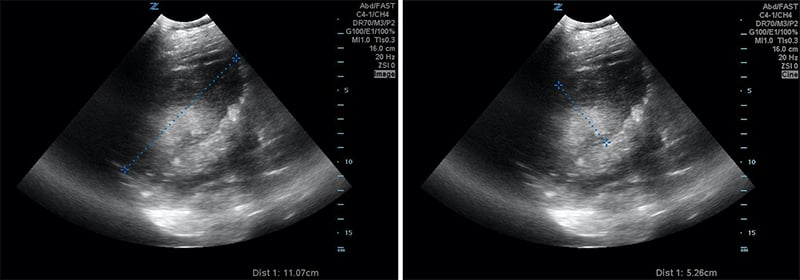

Figures 30A & B. Suprapubic views revealing no fetal cranium in the pelvis. While in some cases like this transverse view of a breech presentation (A) and this sagittal view of a transverse presentation (B), it may be difficult to exactly determine the fetal anatomy, the lack of the fetal cranium is adequate to rule out a vertex presentation and should increase the clinician’s suspicion for a more difficult delivery.